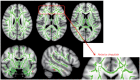

Results: The patients with MCI exhibited significant improvements in the trail-making test-black & white-B, and memory domain of the computerized cognitive assessment. Subjects with normal cognition exhibited significant improvements in scores in the language and attention-/psychomotor-speed domains. There were no significant changes in subjects with SMI. In the pre- and posttraining evaluations of the MCI group, FDG-PET showed focal activation in the left anterior insula and anterior cingulate after training. Volumetric MRI showed a focal increase in the cortical thickness in the rostral anterior cingulate. DTI revealed increased fractional anisotropy in several regions, including the anterior cingulate.

Conclusions: The anterior cingulate and anterior insula, which are parts of the salience network, may be substrates for the improvements in cognitive function induced by computerized cognitive training.